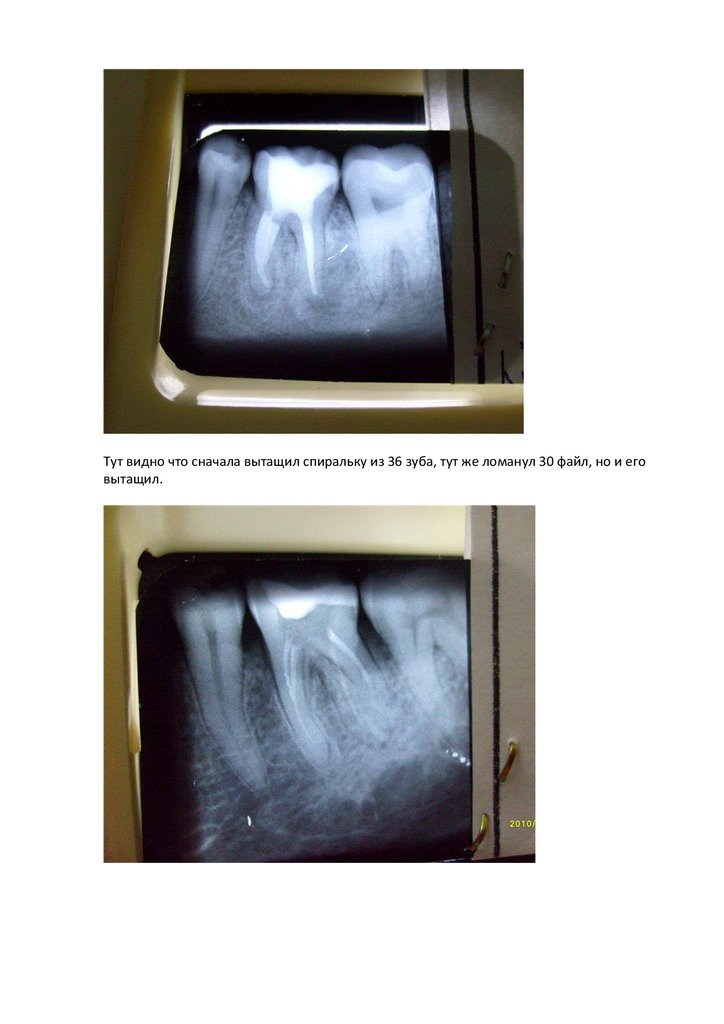

Тут видно что сначала вытащил спиральку из 36 зуба, тут же ломанул 30 файл, но и его

вытащил.

Это он же после убирания бором лохмотьев из устьев и еще не отмытый